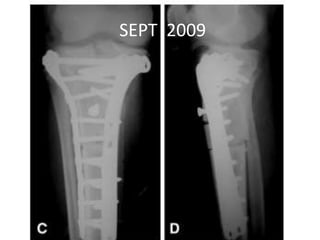

SEPT 2009

• MAY 2013 •DENOSUMAB started • 360 mg subcutaneous dose • Followed by 120 mg every month

• Pain aroundknee joint diminished • Further resection ?? • Patient refused • Clinical improvement persisted until jan 14 • Presented with Rapidly growing painful palpable mass • Open biopsy : high grade sarcoma • A/K amputation